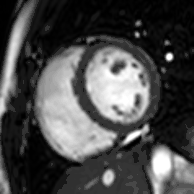

Heart function using cine imaging

Functional and structural information is acquired using bSSFP cine sequences. These are usually retrospectively-gated and have intrinsically high contrast in cardiac imaging due to the relatively high T2:T1 ratio of blood compared to myocardium. Images are typically planned sequentially to achieve the standard cardiac planes used for assessment. Turbulent flow causes dephasing and signal loss allowing valvular disease to be qualitatively appreciated. The left ventricular short axis cines are acquired from base to apex and are used for quantifying end-diastolic and end-systolic volumes, as well as myocardial mass. Tagging sequences excite a grid pattern that deforms with cardiac contraction allowing strain to be assessed.